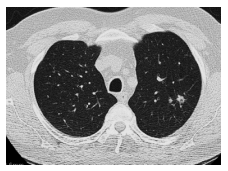

Paciente feminina de 22 anos procura

atendimento por hemoptise eventual, tosse

produtiva e pneumonias frequentes (em

média 3 por ano). Durante avaliação, foi

solicitada tomografia de tórax. Referente às

alterações presentes na seguinte imagem,

assinale a alternativa correta.